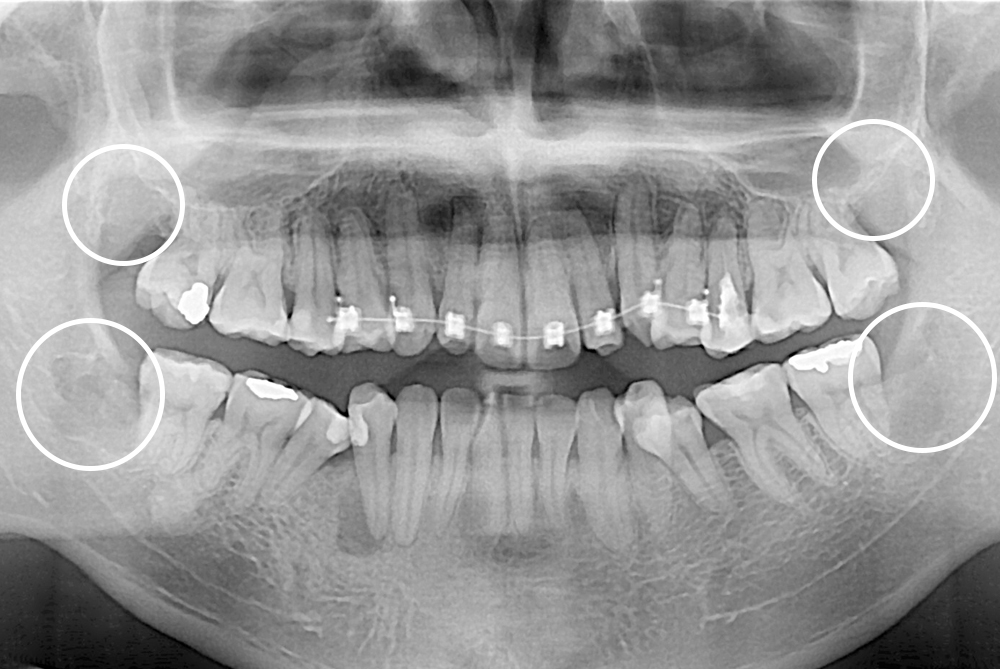

[사랑니] 매복 사랑니 발치

치료후 : 2018-03-09

세종치과는 구강악안면외과학 박사이신 원장님이 발치하는 치과입니다.